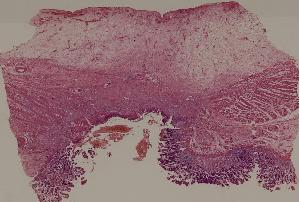

60. Gastric ulcer